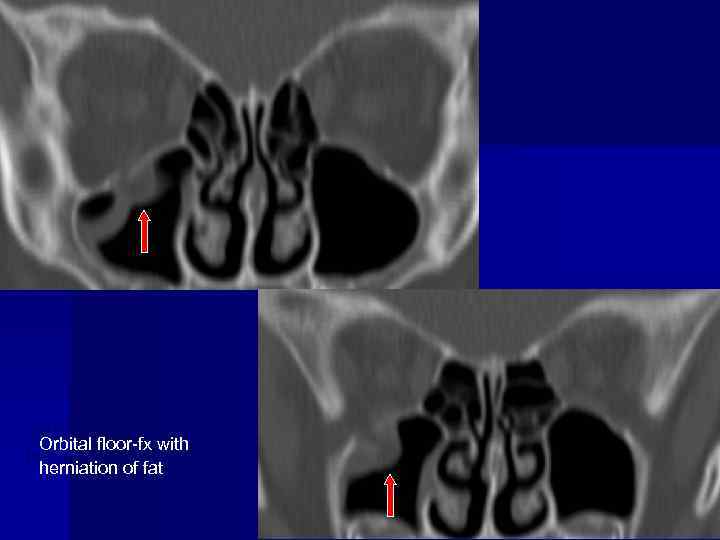

Facial trauma blow-out fracture

Orbital floor-fx with herniation of fat